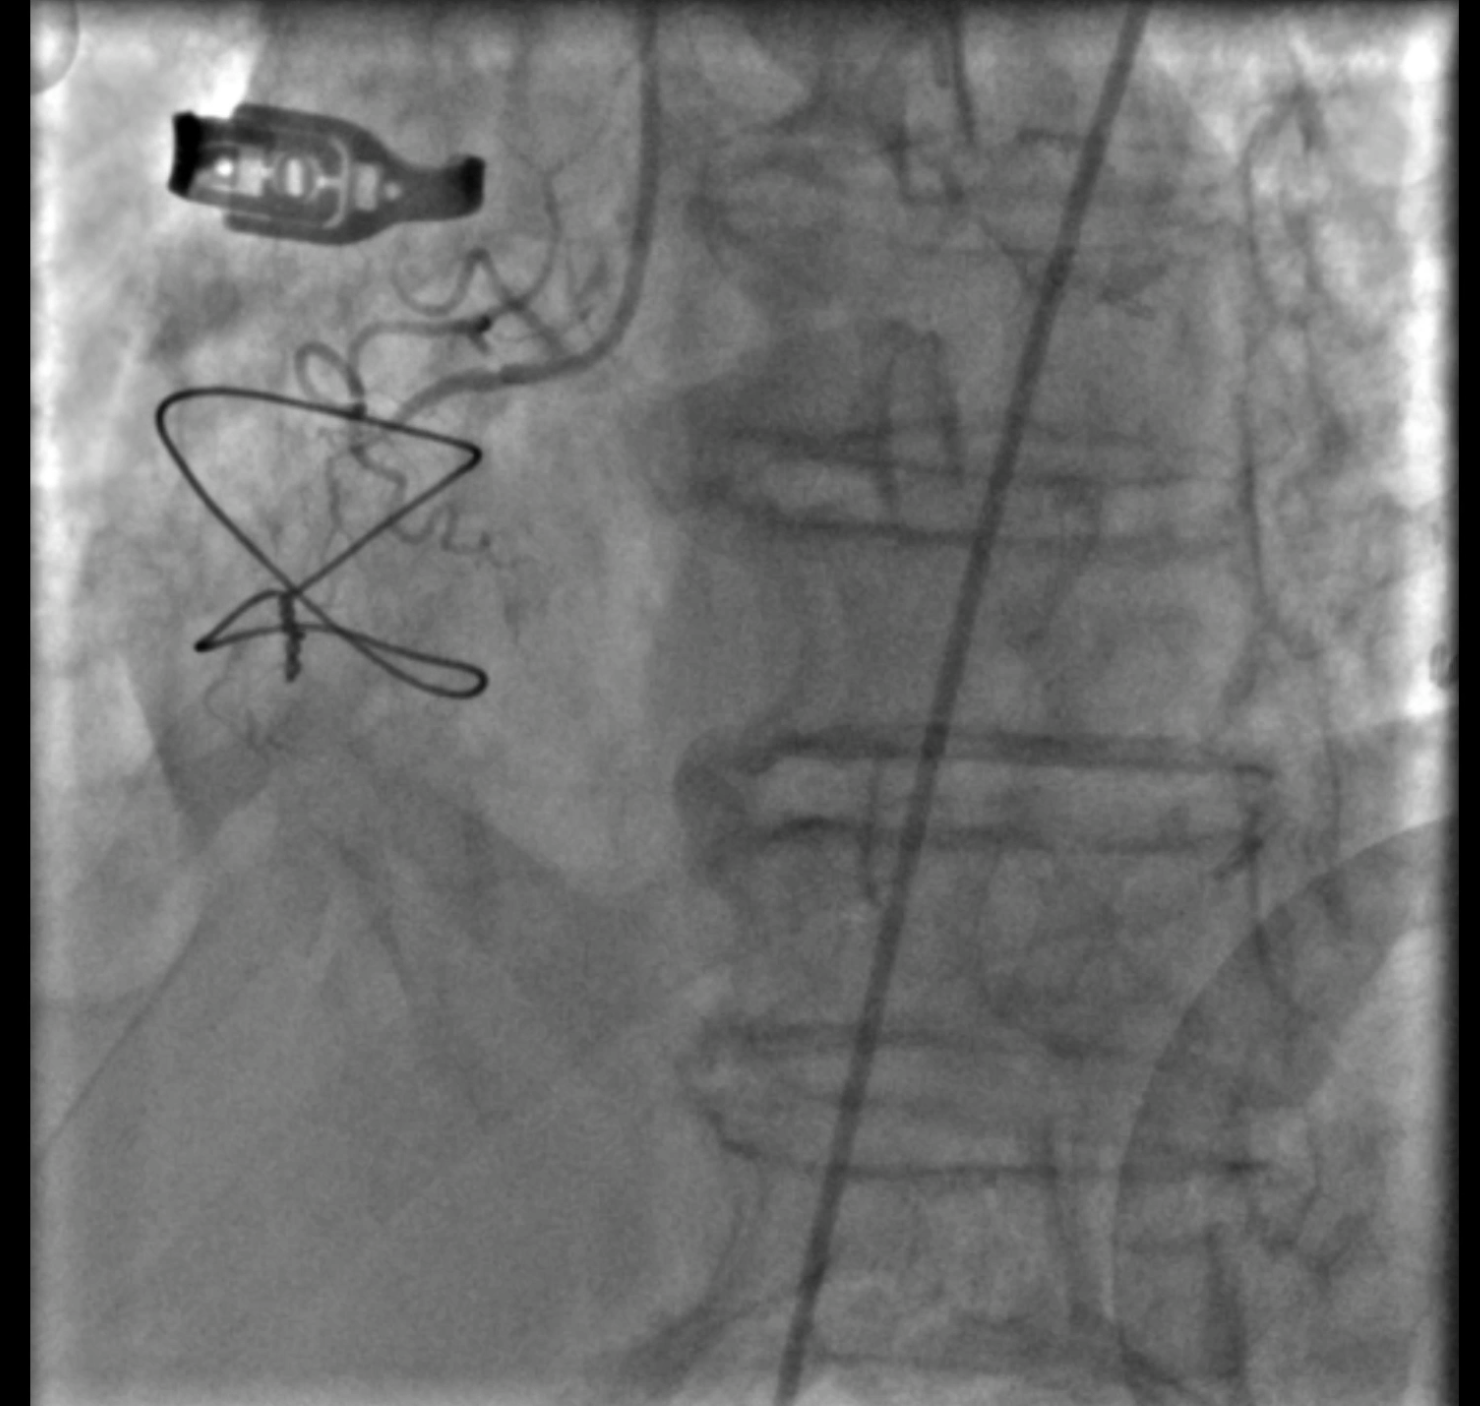

At the first encounter, coronary angiography revealed a left main bifurcation lesion (Medina 1-1-1) with 99% ostial stenosis of the LCX and severe stenosis in the proximal LAD and the 2nd diagonal branch. Collateral circulation was observed from the LAD and LCX to the distal RCA. Right coronary angiography showed a proximal CTO with a J-CTO score of 3 due to calcification, bending, and lesion length. The LIMA was not grafted to the LAD.

At the 1st encounter, RCA CTO PCI was performed with a plan for staged PCI of the left system. Using a 7F AL 0.75 for strong support, an antegrade approach with a double-lumen microcatheter and parallel wire technique (Pilot 150) successfully crossed the lesion. Predilatation with a 1.5 ¡¿ 15 mm balloon was done. IVUS could not pass due to 360¡Æ calcification. Rotablation with a 1.25 mm burr was attempted but limited to mid-RCA. Two DES were implanted from mid to proximal RCA, followed by post-dilatation.At the 2nd encounter, RCA stents were patent. PCI was done on LM, LAD, and D2. D2 was treated with DCB. LAD predilatation followed by OCT showed severe 330¡Æ calcification (max thickness 1.04 mm, MLA 1.63 mm©÷). IVL with a 2.75 ¡¿ 12 mm balloon (30 pulses) achieved multiple calcium fractures. A 2.75 ¡¿ 33 mm DES was deployed with good OCT results.At the 3rd encounter, 6 months later, the patient presented with ADHF. Angiography revealed RCA ISR CTO at the mid-bending site. The lesion was crossed with a Pilot 200 wire; predilatation showed a dog-bone sign. We do balloon based strategy for plaque modification using cutting, scoring, and double-wire balloons. IVUS showed stent underexpansion with 270¡Æ calcification and distal RCA stenosis. IVL with 2.5 and 2.75 mm balloons optimized the lesion, followed by two DES from distal to mid RCA. Post-PCI IVUS confirmed good result.